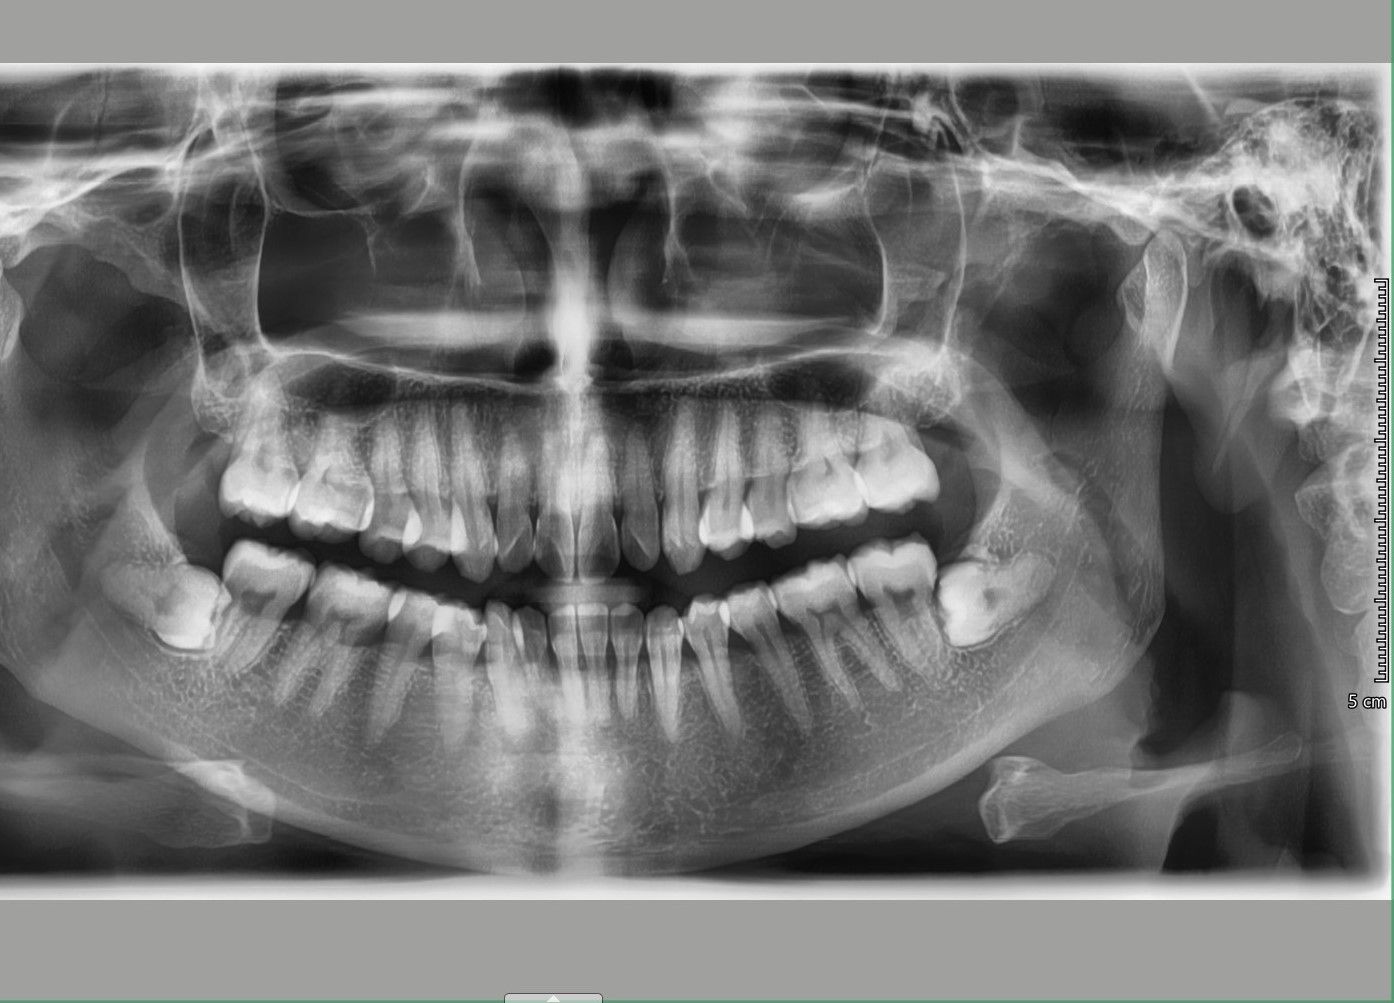

Nên niềng mắc cài hay invisalign cho tình trạng răng khấp khểnh vùng răng cửa, hô ở mức trung bình

Xin chào các bác sỹ Em đã đi tư vấn, các nha khoa đều đưa ra 2 lựa chọn mắc cài hoặc invisalign. Vậy em xin hỏi với trường hợp của em, phương pháp nào tối ưu, hiệu quả, tiết kiệm thời gian và an toàn hơn? Em cảm ơn.

Có thể khắc phục được tình trạng răng chen chúc xô lệch mà không cần nhổ răng không?

Tôi 23 tuổi và đang cân nhắc đến việc niềng răng để khắc phục tình trạng răng mọc khấp khểnh. Tôi đã đến gặp hai bác sĩ nha khoa thẩm mỹ và họ đều nói là cần phải nhổ răng nhưng tôi lại không muốn vậy. Hàm dưới của tôi gần như hoàn hảo nhưng tôi có tật nghiến răng vào ban đêm. Vậy tôi muốn hỏi là có thật sự cần phải nhổ răng hay không?